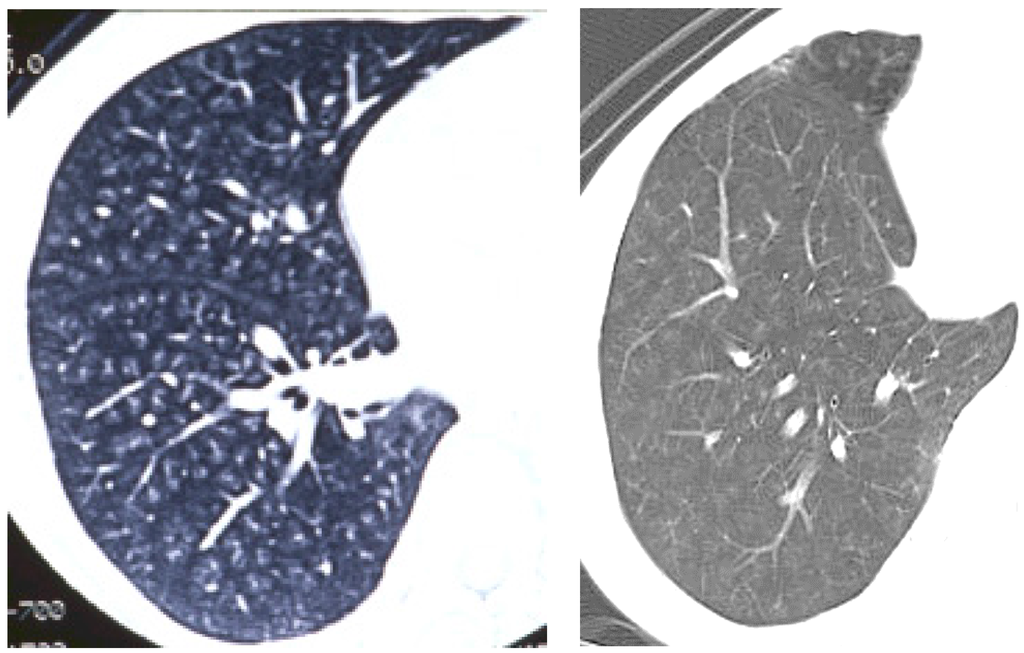

As for human data, there are some reports that exposure to welding fumes including nanoparticles induced pneumoconiosis [24,25,26], although there is no report on exposure to nanoparticles only. The distribution of welding fume deposition in the lung was in a centrilobular pattern [27] (Figure 3). Therefore the distribution of nanoparticle deposition in intratracheal instillation studies may not be very different from that in inhalation studies and human exposure. However, unless the process of dispersion of nanoparticles is performed, agglomerates of nanoparticles might be deposited in the large bronchiole and not come into the lung. It is necessary that the dispersion of nanoparticles be confirmed.

Figure 3. Pictures of chest in patients with welder’s lung using chest computed tomography. Nodular opacities (diffuse white opacities in the lung) were mainly observed in centrilobular lesions in the lung.